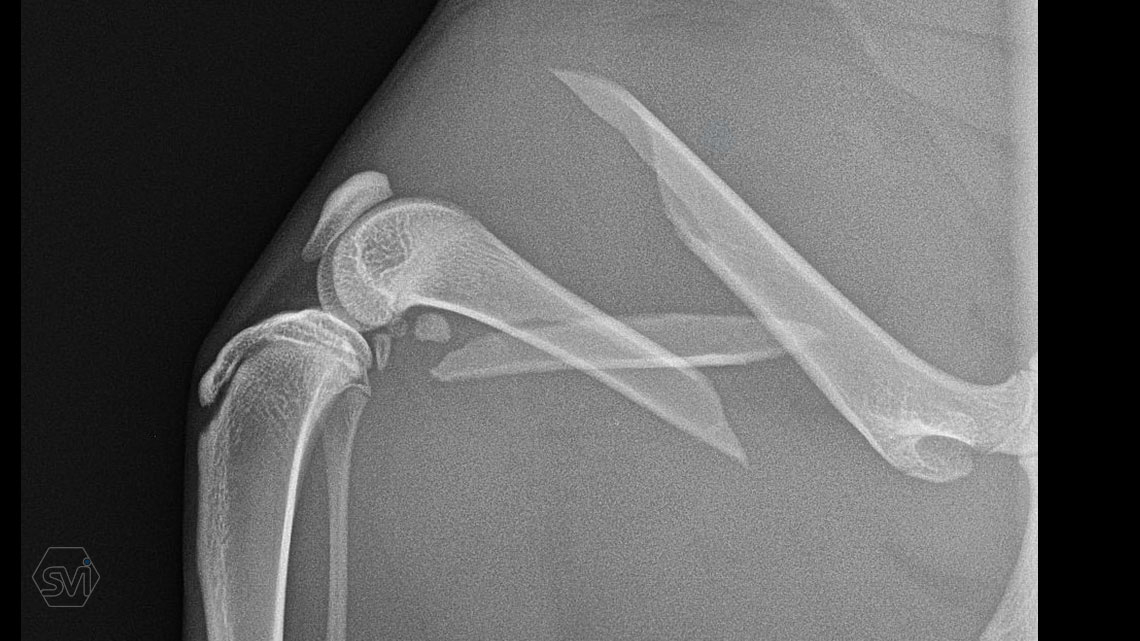

In our case, a middle third fragment fracture of a 10-month-old kitten was treated with a 2.0 polyaxial plate and a combination of 2.0 and 2.4 screws.

The plates are made in two types: the cutable ones, presented earlier, and the straight plates discussed here. The plates are made of 2 mm thin material and the hole is designed to accept the new 2.0 mm torx head threaded screws and the already used 2.4 mm torx head screws. As our case shows, the two screw sizes can be freely combined within one operation, according to the surgeon's needs. The screws require a T8 torx screwdriver. Of course, the plate can accept traditional AO screws as well.